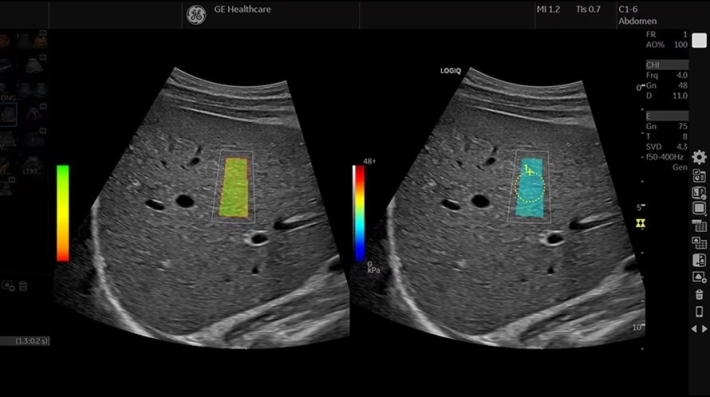

• ShearWave Elastography — опция эластографии «сдвиговой волны»;

• Elastography Imaging Option — программа компрессионной эластографии;

• Q-analysis Option for Elastography and CF/PDI Quantification — программа количественного анализа для эластографии и анализа васкуляризации;